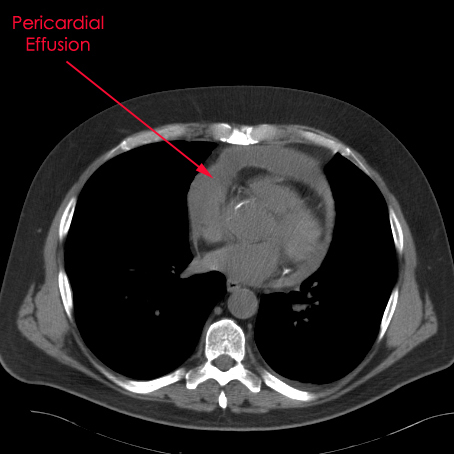

| Figure 1. CT scan showing pericardial effusion. |

Hemodynamically stable patients with an undiagnosed pericardial effusion are well suited for a thoracoscopic window. When pericardial, pleural, or pulmonary pathology co-exist and require diagnosis or therapy, a thoracoscopic approach is ideal. If a large piece of pericardial tissue is needed for culture or pathological examination, thoracoscopy provides good exposure and allows for an adequate specimen to be sampled [1]. Known benign effusions that re-accumulate after aspiration should be treated with a thoracoscopic window. Drainage of a purulent pericardial effusion, and early fungal or tuberculous pericarditis where resection of the pericardium to prevent future pericardial constriction is required, are also indications. In patients with descending mediastinitis a window or resection of the pericardium may be warranted as part of the mediastinal debridement. Loculated effusions situated unilaterally or posteriorly are more easily approached thoracoscopically (Figure 1).

A CT scan provides information as to the location and size of the effusion, whether there are loculations, the nature of the parietal pericardium, and associated pulmonary or pleural pathology. Echocardiography provides a dynamic assessment of the physiologic impact of the effusion on myocardial function which helps determine if the patient will be hemodynamically stable to undergo a thoracoscopic pericardial window (Echo 1).